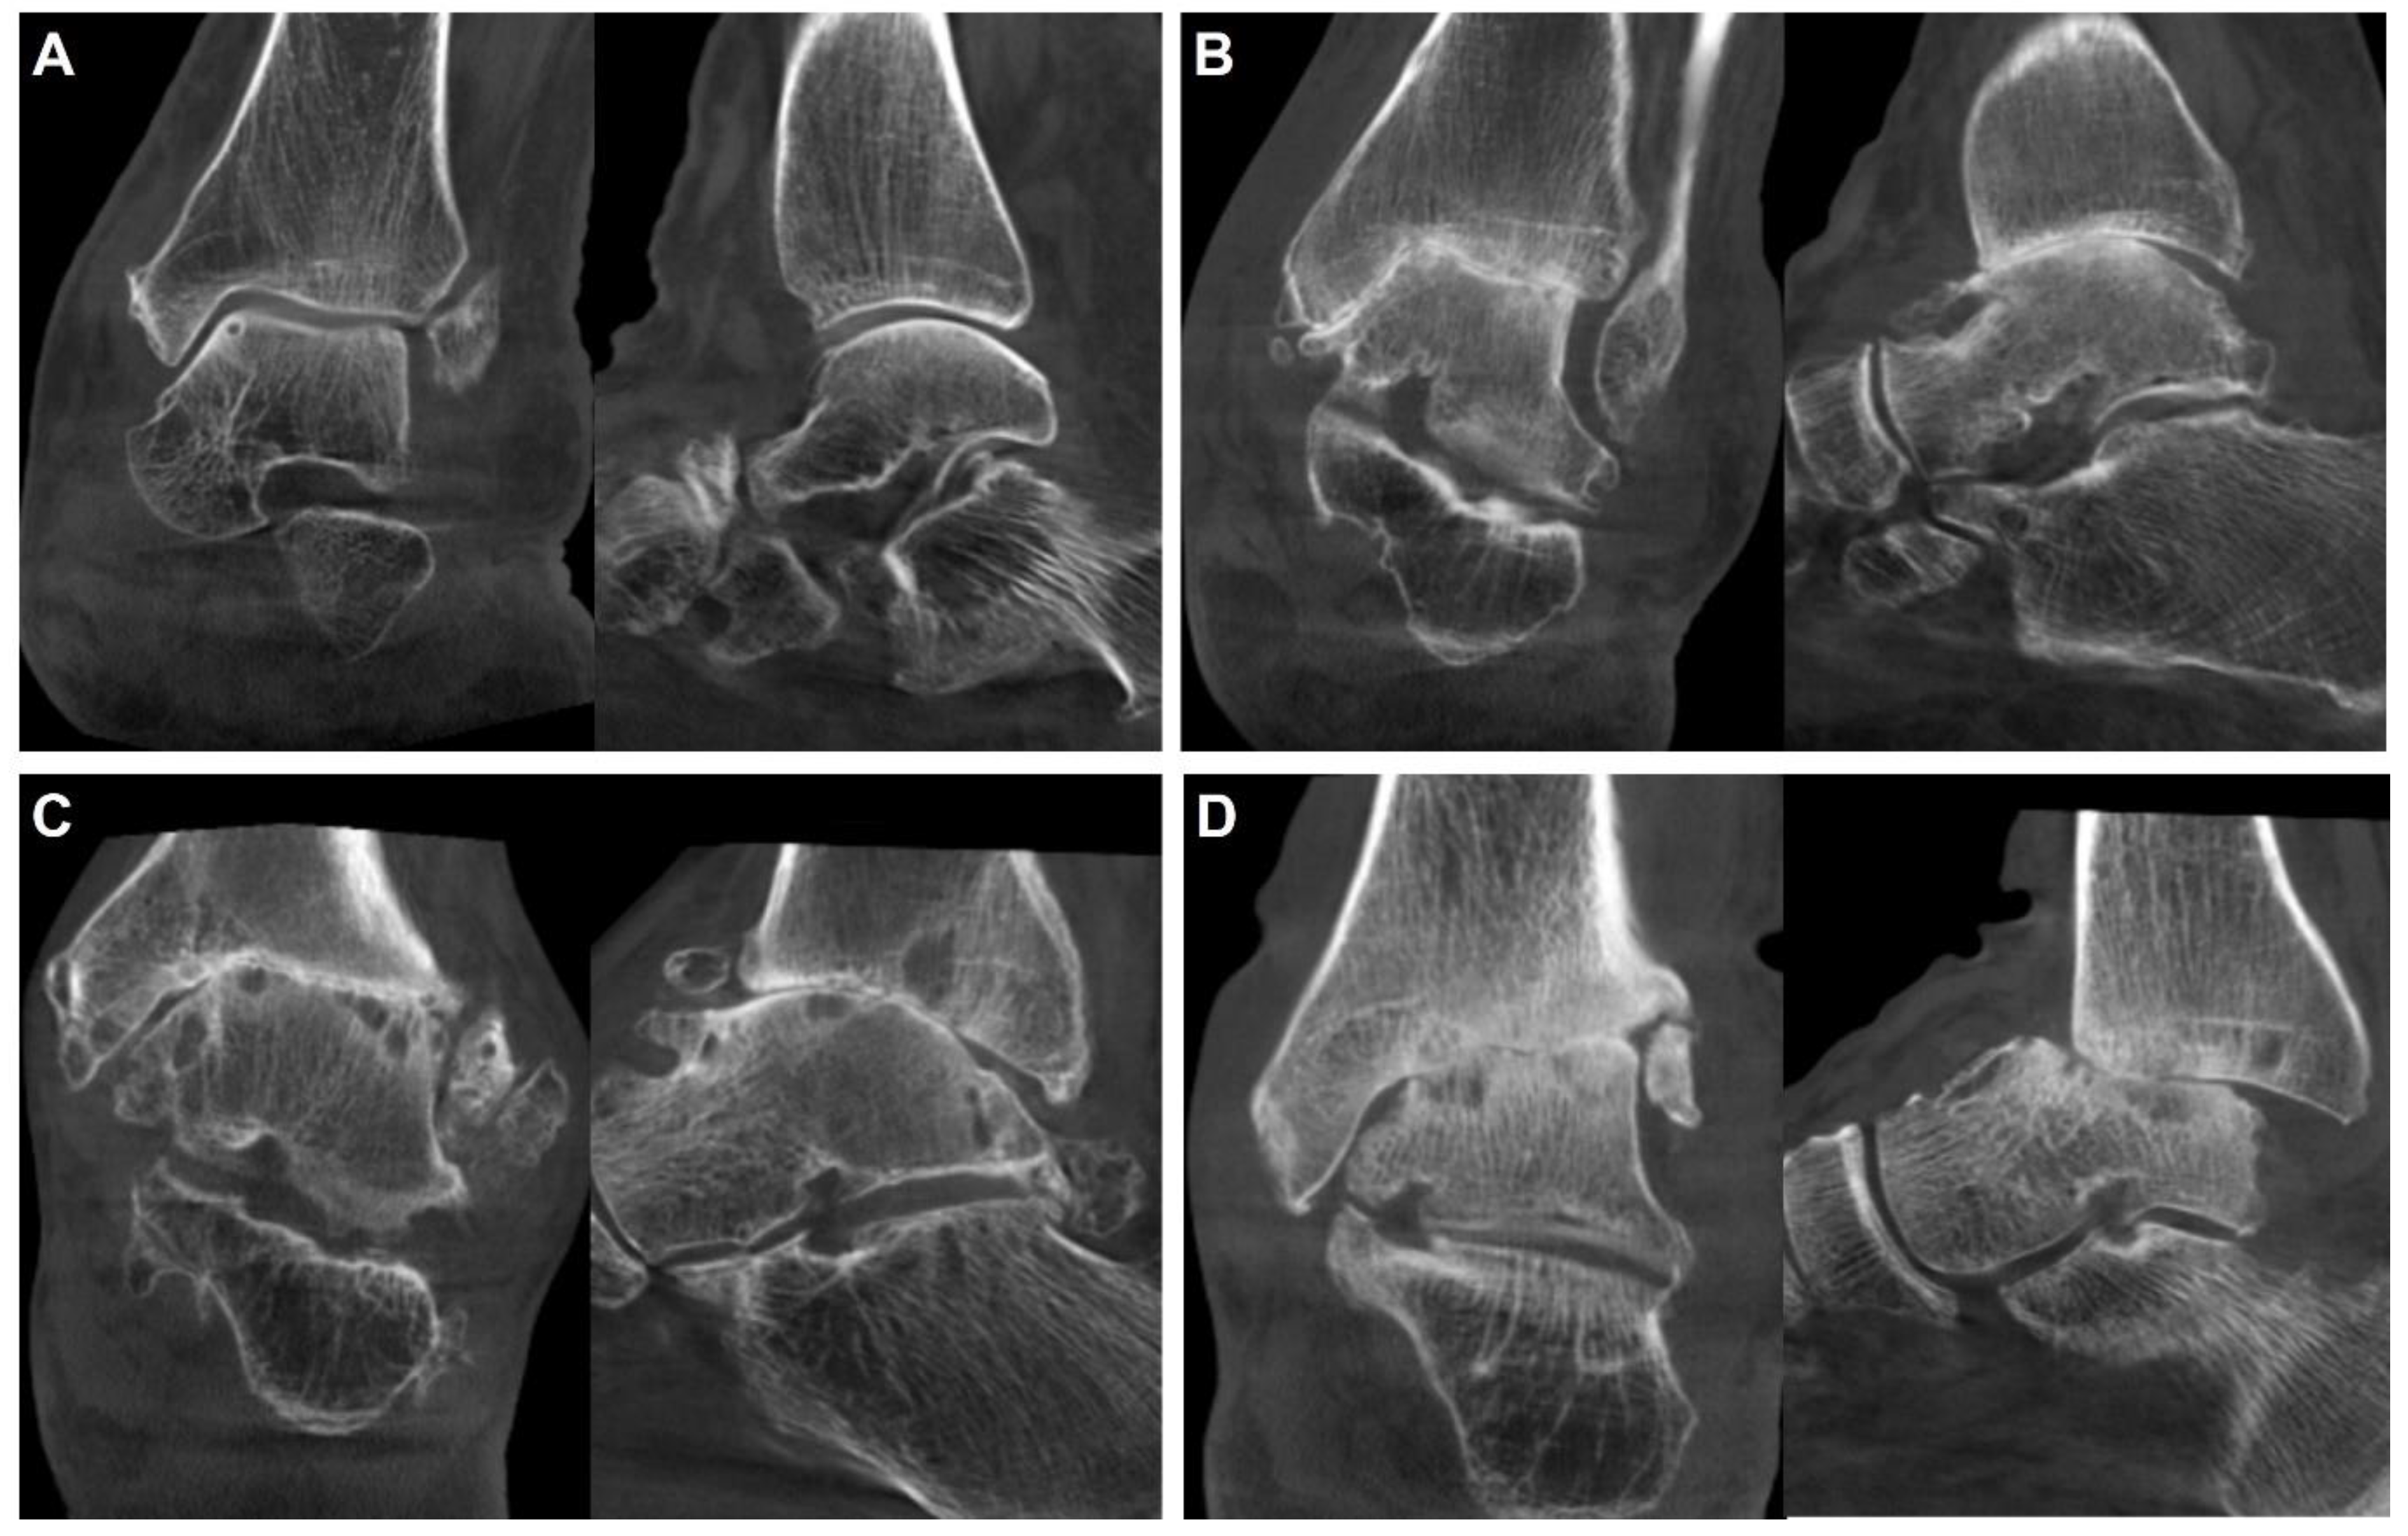

- Ankle Osteoarthritis

- Osteochondral lesion of talus

- Chronic ankle instability

- Acute ankle sprain